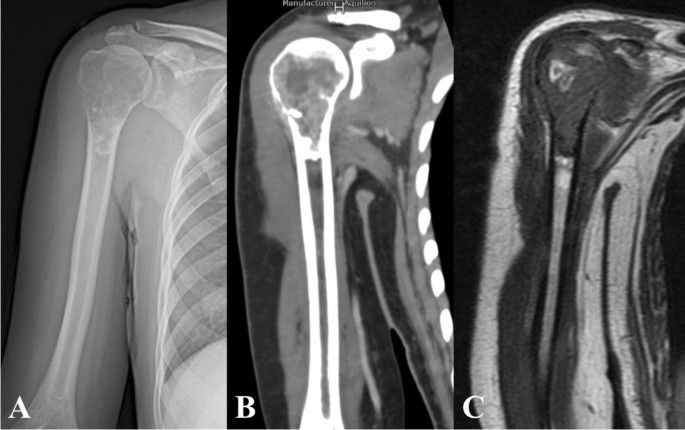

Clinical diagnosis

All patients received radiography, CT and MRI of proximal humerus (Fig. 1) and whole body bone scanning before operation. The diagnosis was confirmed as primary malignant bone tumor by preoperative biopsy. The patients with osteosarcoma and Ewing sarcoma received preoperative chemotherapy.